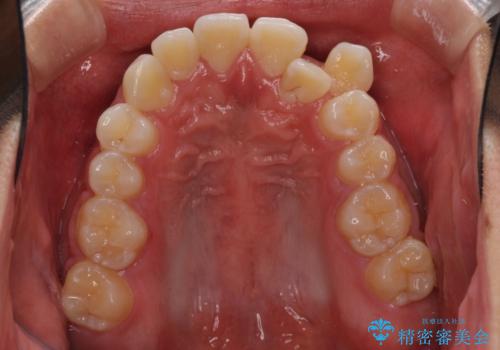

八重歯と奥歯のクロスバイト 上顎骨を拡大してインビザラインで矯正

- 八重歯を気にして来院された患者様です。

八重歯が著しいため、抜歯矯正も視野に入れて検討しましたが、臼歯の咬合関係は正常に近かったので、非抜歯矯正で進める方針としました。

上顎骨の幅が狭く、奥歯がクロスバイトとなっていたため、急速拡大装置を用いて上顎骨を側方拡大し、八重歯を収めるスペースを獲得しつつクロスバイトを改善することとしました。

上顎骨を思い通りに拡大できたため、当初の計画通りに非抜歯矯正で仕上げることができました。